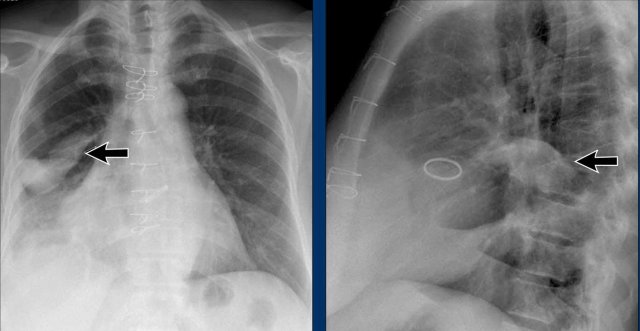

First study the PA and lateral chest film and then continue reading.

Findings

• Chest radiographs show massive cardiomegaly, predominantly due to right ventricular dilation (yellow arrow on lateral view).

• Small aortic knob (blue arrow), with dilation of the pulmonary trunk and right lower pulmonary artery.

• Findings suggest a left-to-right shunt with secondary pulmonary hypertension.